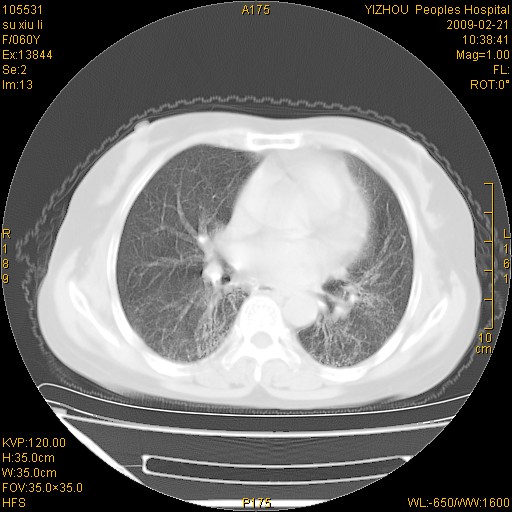

标题: CT18259:两肺间质纤维化? [打印本页]

标题: CT18259:两肺间质纤维化?

女,60岁,反复咳嗽1月。

两肺支扩,以肺为著合并双肺较广范纤维化病变。建议除外结核等病变。

间质性肺炎

两下肺支扩

符合间质感染,部分纤维化表现

特发性间质纤维化

特发性间质纤维化伴支扩!

间质性肺炎或特发性间质性肺炎